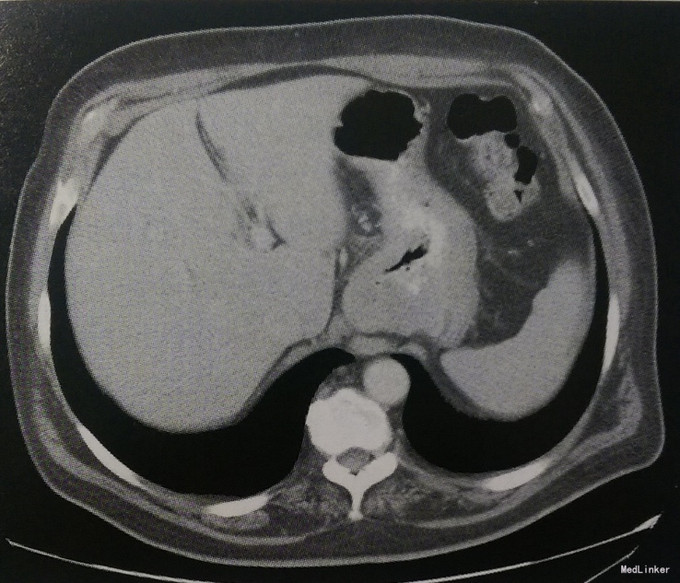

体格检查: T37.1℃。BP137/84mmHg,P104次/分。头颅和五官:无黄疸,口咽部干净,无腺体肿大。心脏:正常心率,心律齐。肺部:听诊呼吸音清。腹部:肠鸣音正常,腹柔软,无触痛,无膨隆,无脏器肿大。四肢:无水肿及发绀,无杵状指(趾)。 实验室检查: 血常规:白细胞11100/μl,分类正常,血红蛋白10.4g/dl,MCV74fl,血小板456000/lμl。生化检查:正常。肝功能:正常。胸部X线检查:正常。腹部CT:沿胃大弯侧胃壁增厚,无局部淋巴结肿大或肝脏损害。内镜:胃窦部5.7cm×3.8cm肿物。内镜下活检病理学结果:近端胃腺癌。